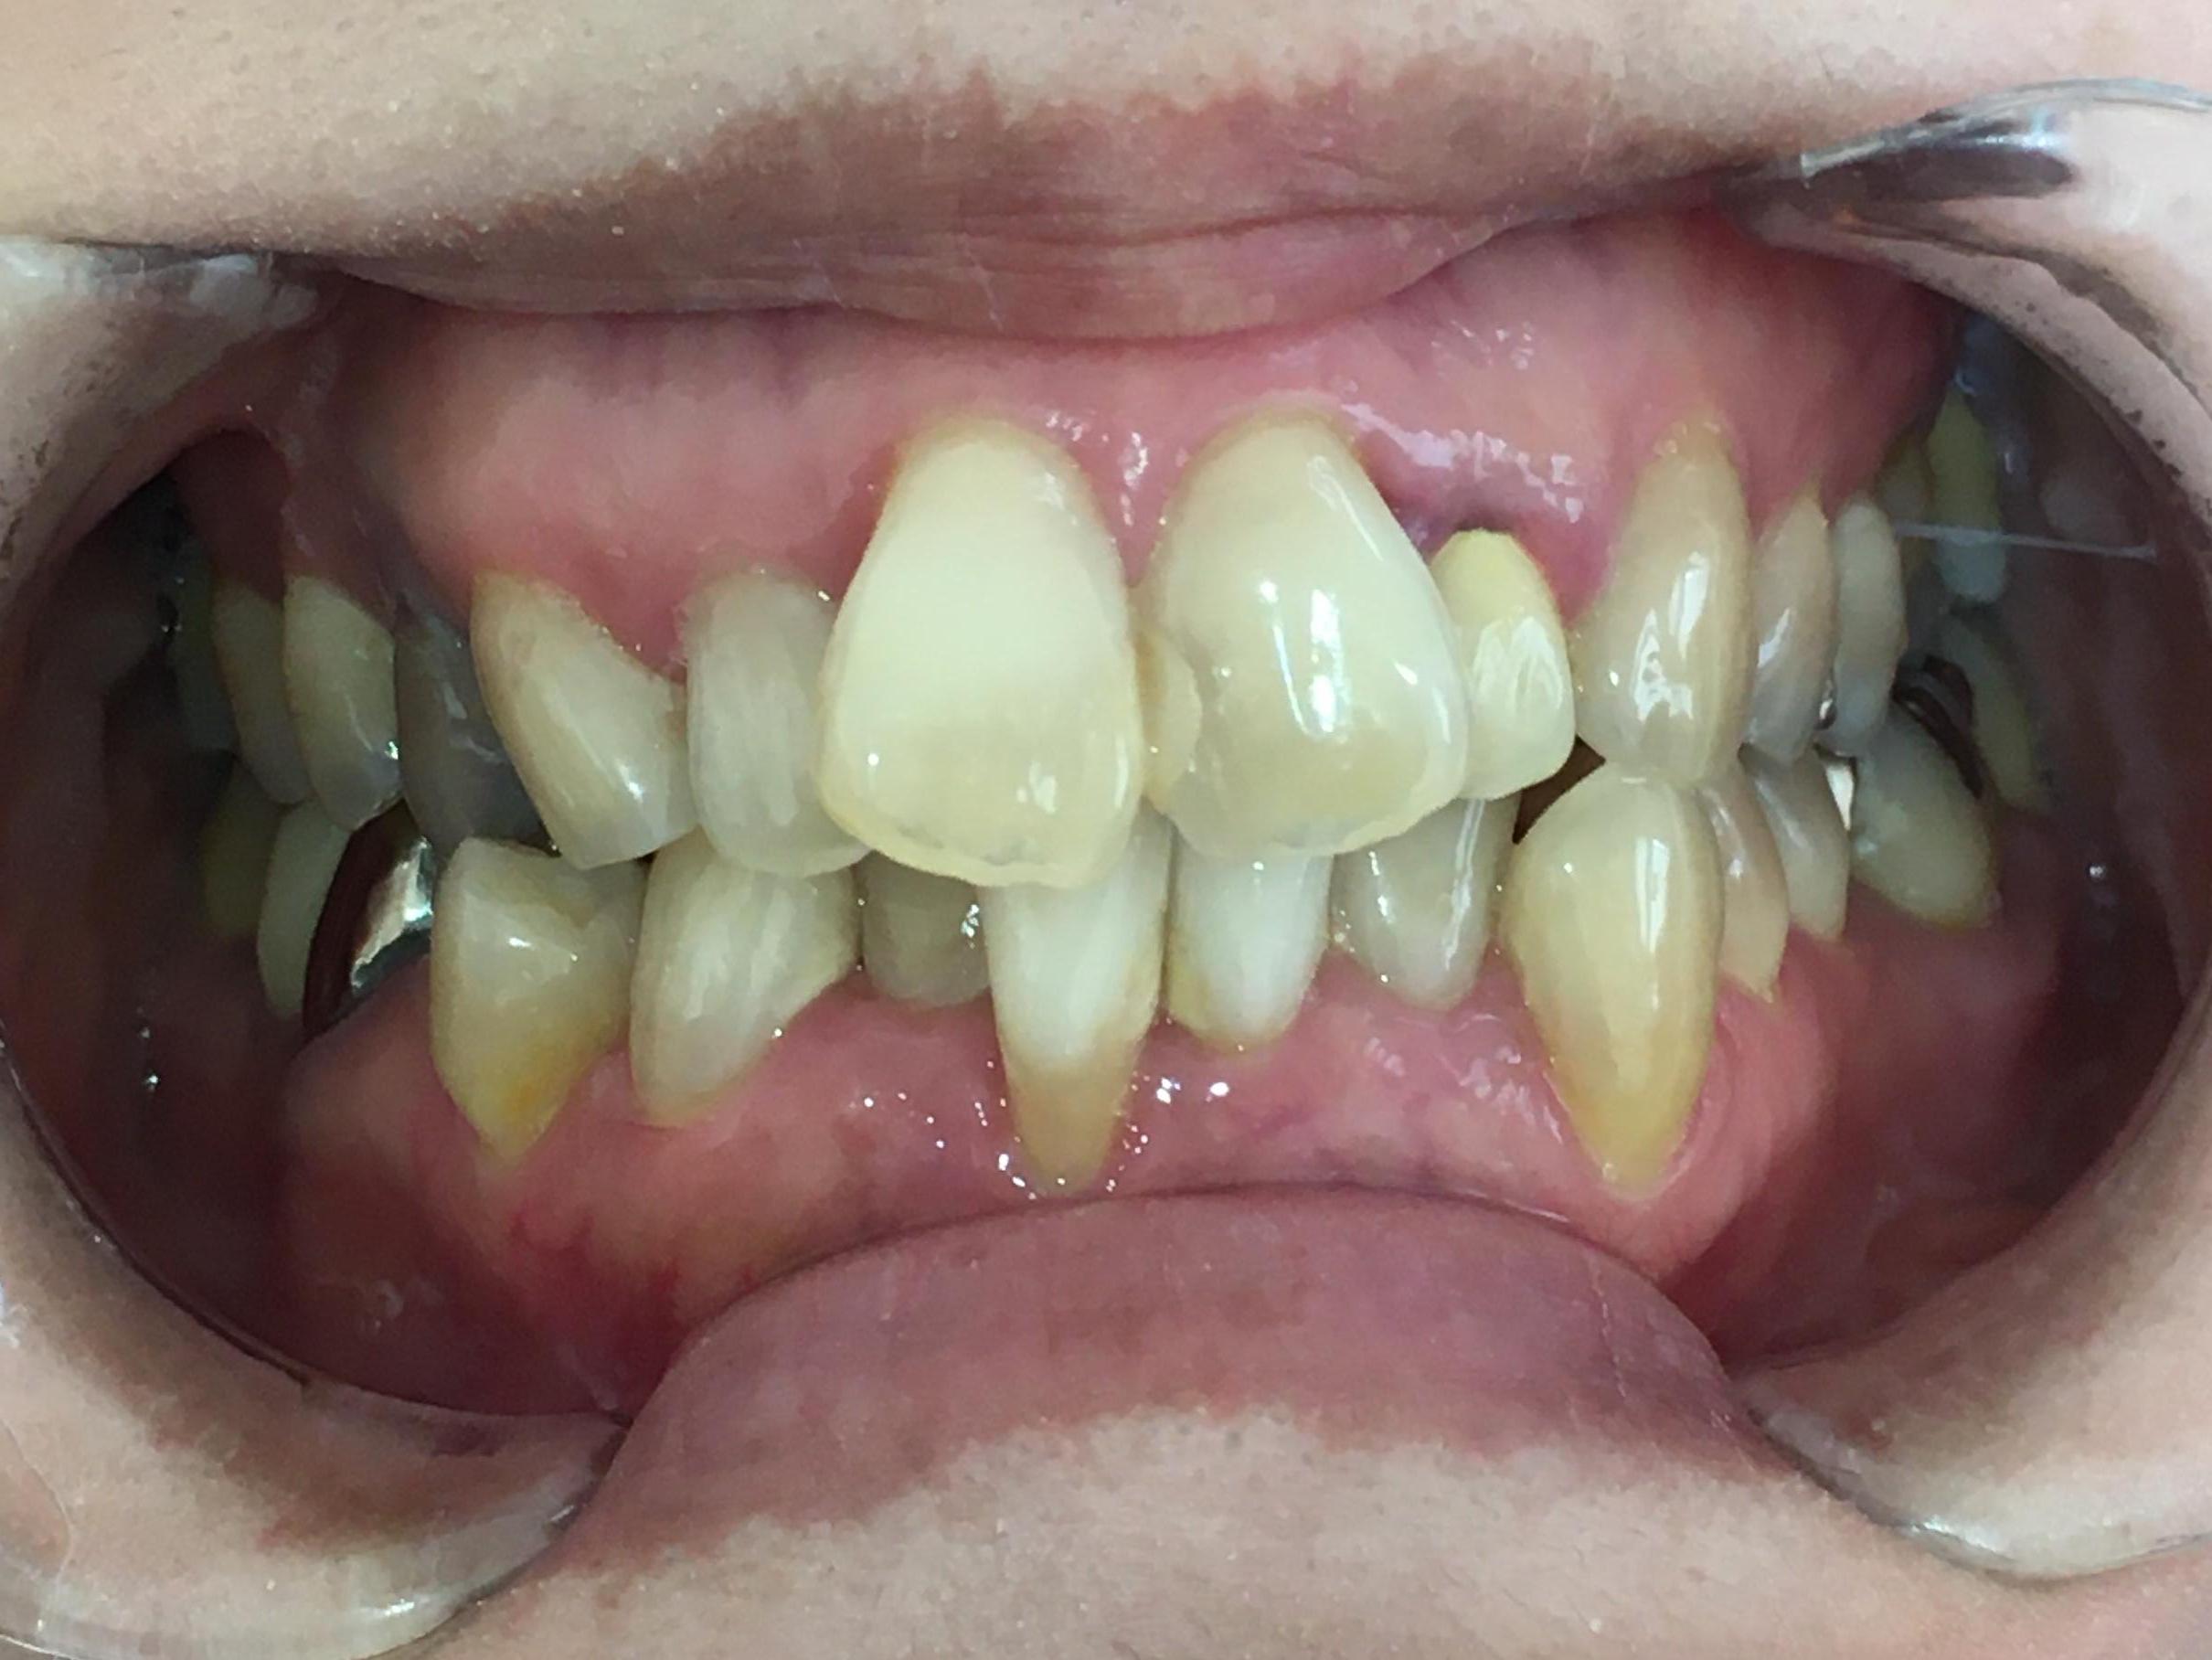

拝見すると、上の前歯が前方に出ている「上顎前突(じょうがくぜんとつ)」でした。

さらに、下左右の前歯6本(中切歯/1番、側切歯/2番、犬歯/3番)は、歯が重なり合って生えている「叢生(そうせい)」で、噛み合わせも悪くなっていました。

また、歯を支えている骨「歯槽骨」が減退する「歯周病」も認められました。